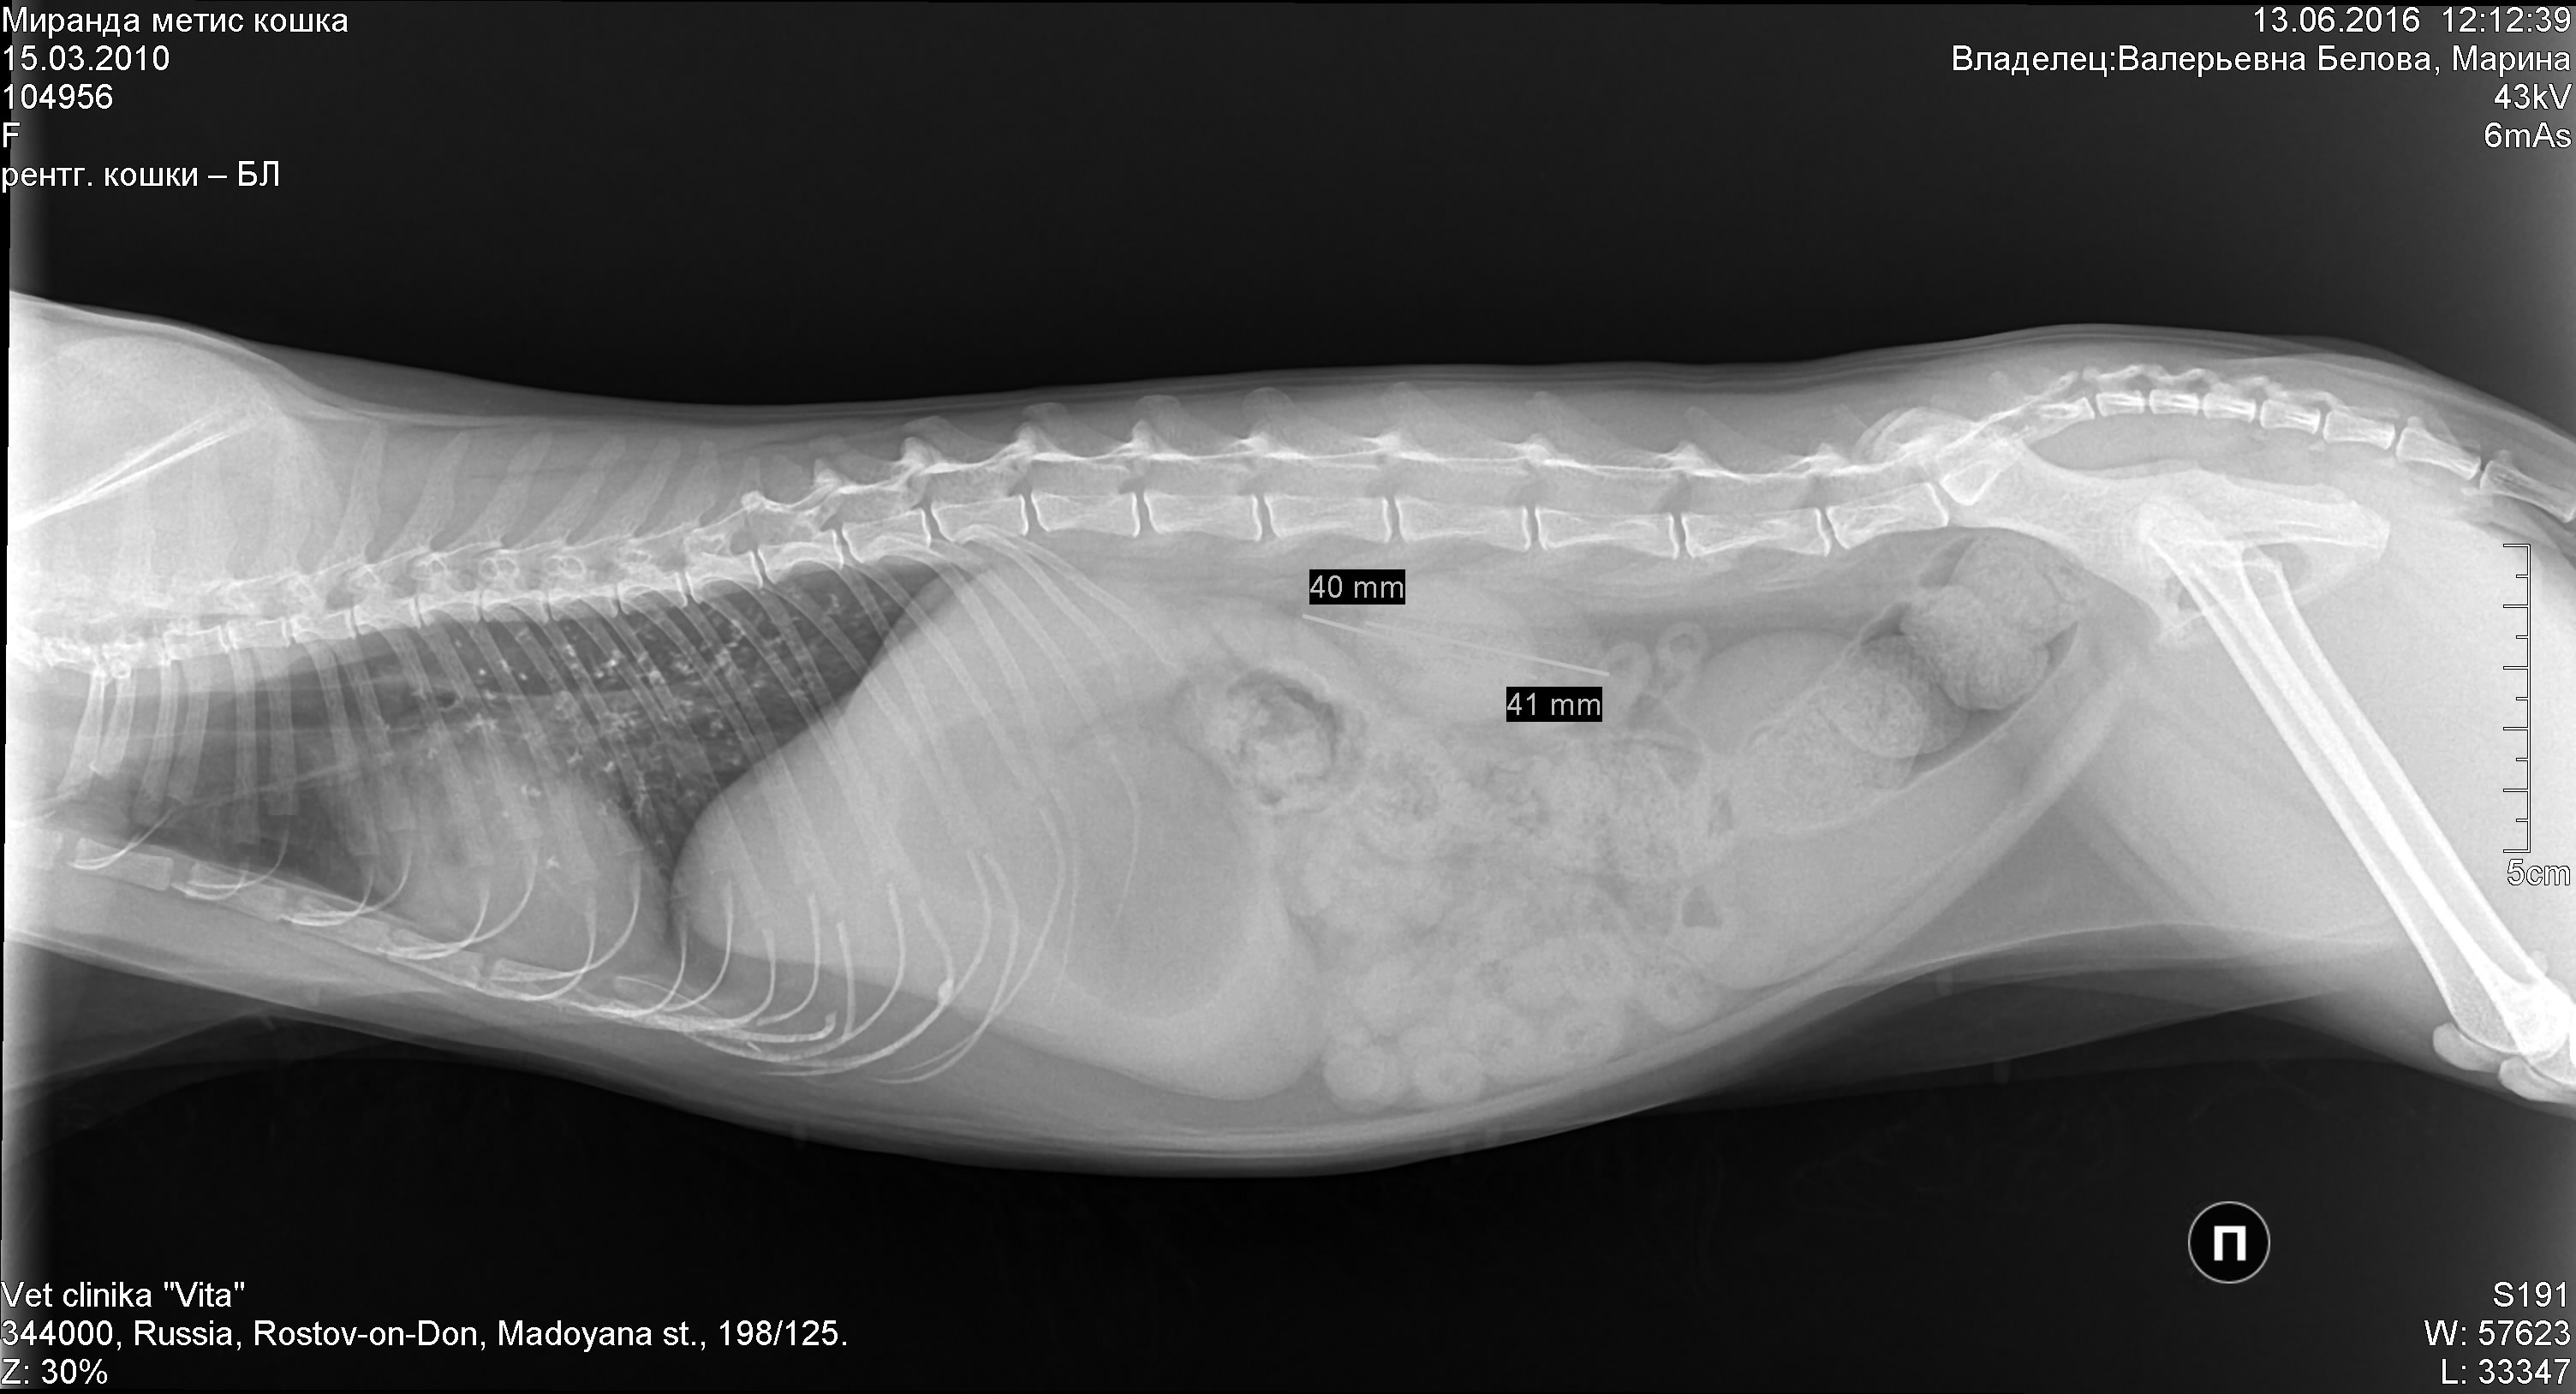

В клинике собаке сделают рентген, который подтвердит или опровергнет отек легких, а также проведут осмотр собаки, прослушают ее и выполнят ряд лабораторных исследований.

Для диагностики отека легких у собак используются такие методы, как аускультация, рентгенография грудной клетки или ультразвуковое исследование, также требуется анализ крови. Электрокардиограмма, анализ мочи и измерение кровяного давления — другие важные тесты, позволяющие выяснить, есть ли у вашей собаки отек легких.

Если состояние вашего питомца стабильное, можно выполнить рентгенографию грудной клетки, положив собаку на спину. На этой рентгенограмме могут быть признаки отека легких, такие как повышенная интерстициальная или альвеолярная непрозрачность. У собак, страдающих кардиогенным отеком легких, также могут наблюдаться кардиомегалия и расширенные легочные вены.

Рентгеновские снимки являются основным инструментом для диагностики отека легких, поскольку они выявляют жидкость внутри легких собаки. Рентген также может выявить увеличенное сердце или другие аномалии сердечной мышцы.